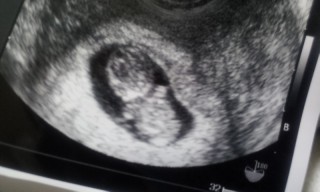

4回目の検診です。CRLは2.67cm

以前より形がハッキリしていて、ダルマみたいな形に!

背骨も見えました!心音も元気にバクバク…安心しました。

予定日は4月1日です。